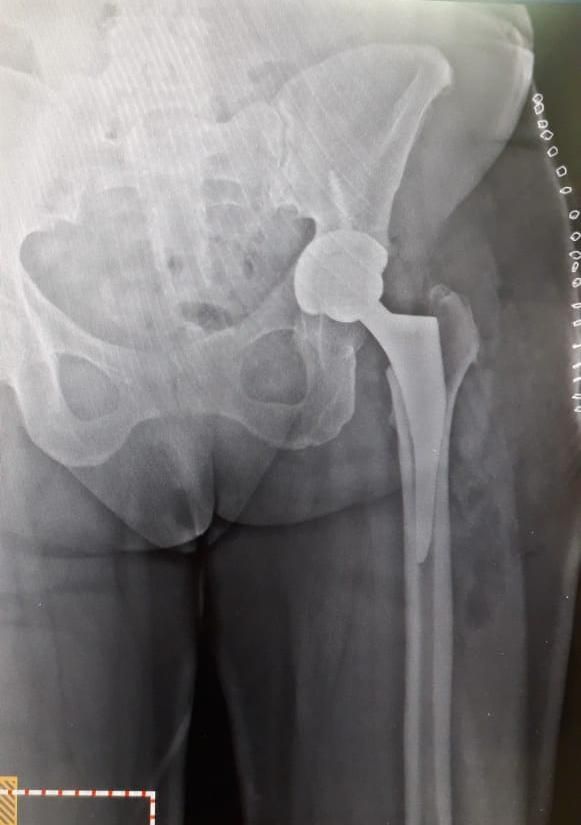

Alta Especialidad en cirugia de Cadera y Pelvis.

- Reemplazo articular de cadera

- Desgaste de cadera

- Fracturas de cadera